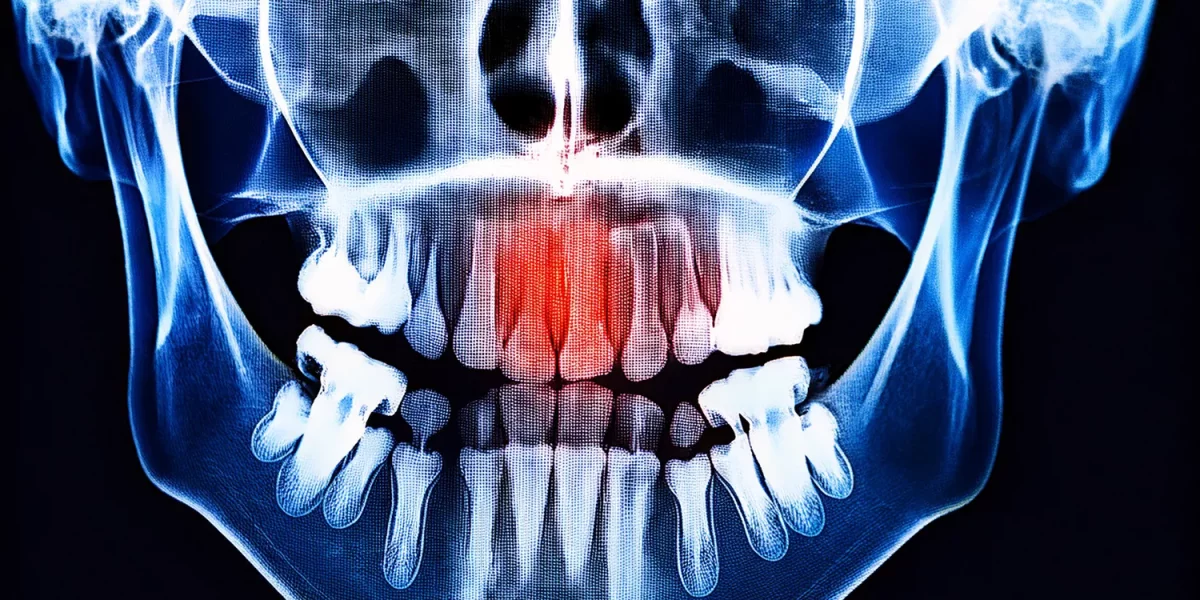

CISTĂ SAU TUMORĂ MANDIBULARĂ? Ce înseamnă „Umbra” de pe radiografia panoramică?

1. Ce este „Umbra” pe o radiografie panoramică?

În primul rând, să clarificăm un punct de bază: Radiografia panoramică este cel mai frecvent radiograf general de screening utilizat în stomatologie, care arată întreaga gură și maxilare într-o singură imagine.

În această imagine:

1. Zonele văzute ca dense, aproape albe: De obicei structuri precum osul, plombele, metalul sau implanturile.

2. Zonele văzute ca mai întunecate, aproape negre: Zone unde densitatea osoasă este redusă sau spații „goale”, cum ar fi cavități chistice/tumorale/normale.

Prin urmare, termenul menționat în raport:

„Radiotransparență” sau „zonă radiotransparentă” înseamnă pur și simplu „o regiune cu aspect întunecat pe radiografie.”

Această zonă întunecată poate fi uneori:

1. Un spațiu anatomic obișnuit (de ex., cavitatea sinusului).

2. O variație normală.

3. O chistă mandibulară care provine de la un dinte.

4. Mai rar, o formațiune tumorală.

Deci, expresia "există o umbră" singură nu înseamnă că ai cancer. Dar este o constatare care trebuie luată în serios și evaluată de un chirurg oral și maxilo-facial.